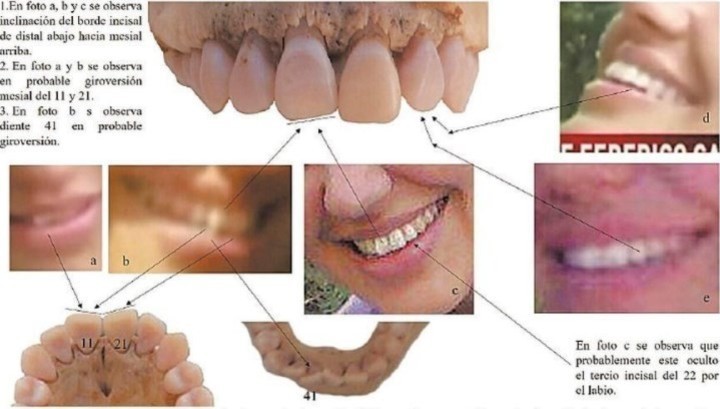

El Tribuno publicó las comparaciones, hechas por el doctor Oscar H. Heit, de Entre Ríos, y su par salteño Pablo Medina en contacto con una dentista forense de Bolivia, que les pidió colaboración para tratar de identificar la dentadura.

Las fotos fueron incorporadas al expediente judicial. Se habla de “múltiples coincidencias”: una grieta en uno de los incisivos, la forma del mentón y las inclinaciones de otras piezas dentarias.